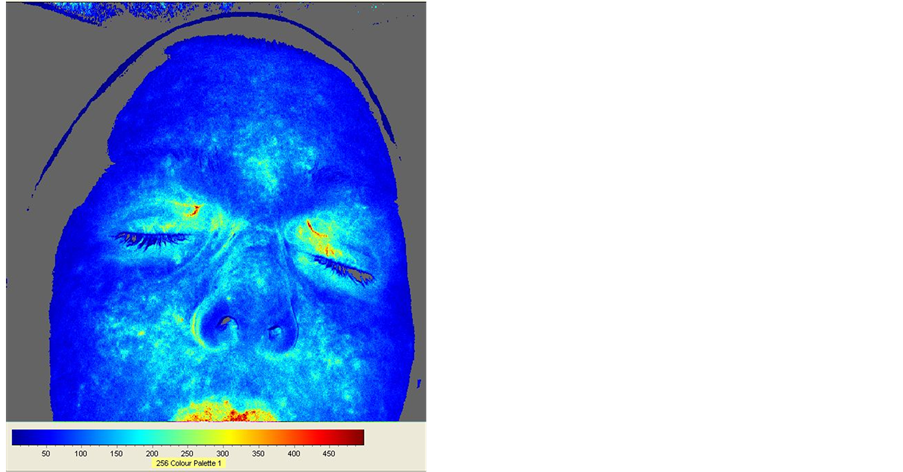

3.2.2. Subject E—Female, Caucasian, 55

Figure 9 shows FBF of subject E at 20 minutes (left image) and 79 minutes (right image). It is apparent that FBF in this sham-grounded subject is lower at 79 minutes. Figure 10 shows variation of mean FBF values over time. Movement artifacts are identified by blue arrows in the top graph of Figure 10 which presents unprocessed mean FBF values. The bottom graph of Figure 10 shows the same graph corrected for artifacts and smoothed. Regression analysis shows that blood flow decreased linearly over time (coefficient of determination R2 = 0.9014) which explains the lower FBF at 79 minutes in Figure 9. No rhythmic pattern of fluctuations in mean FBF values can be observed.

Flux at 20 minutes (frame no 120) Flux at 79 minutes (frame no 474)

Figure 9. Subject E FBF images at 20 minutes (left image) and 79 minutes (right image). There is lower FBF in the right image compared to the left image. Descriptive statistics for the left image: Mean Flux = 103.7; SD = 55.9; Flux min = 0; Flux max = 606. Descriptive statistics for the right image: Mean Flux = 73.0; SD = 46.0; Flux min = 0; Flux max = 730.